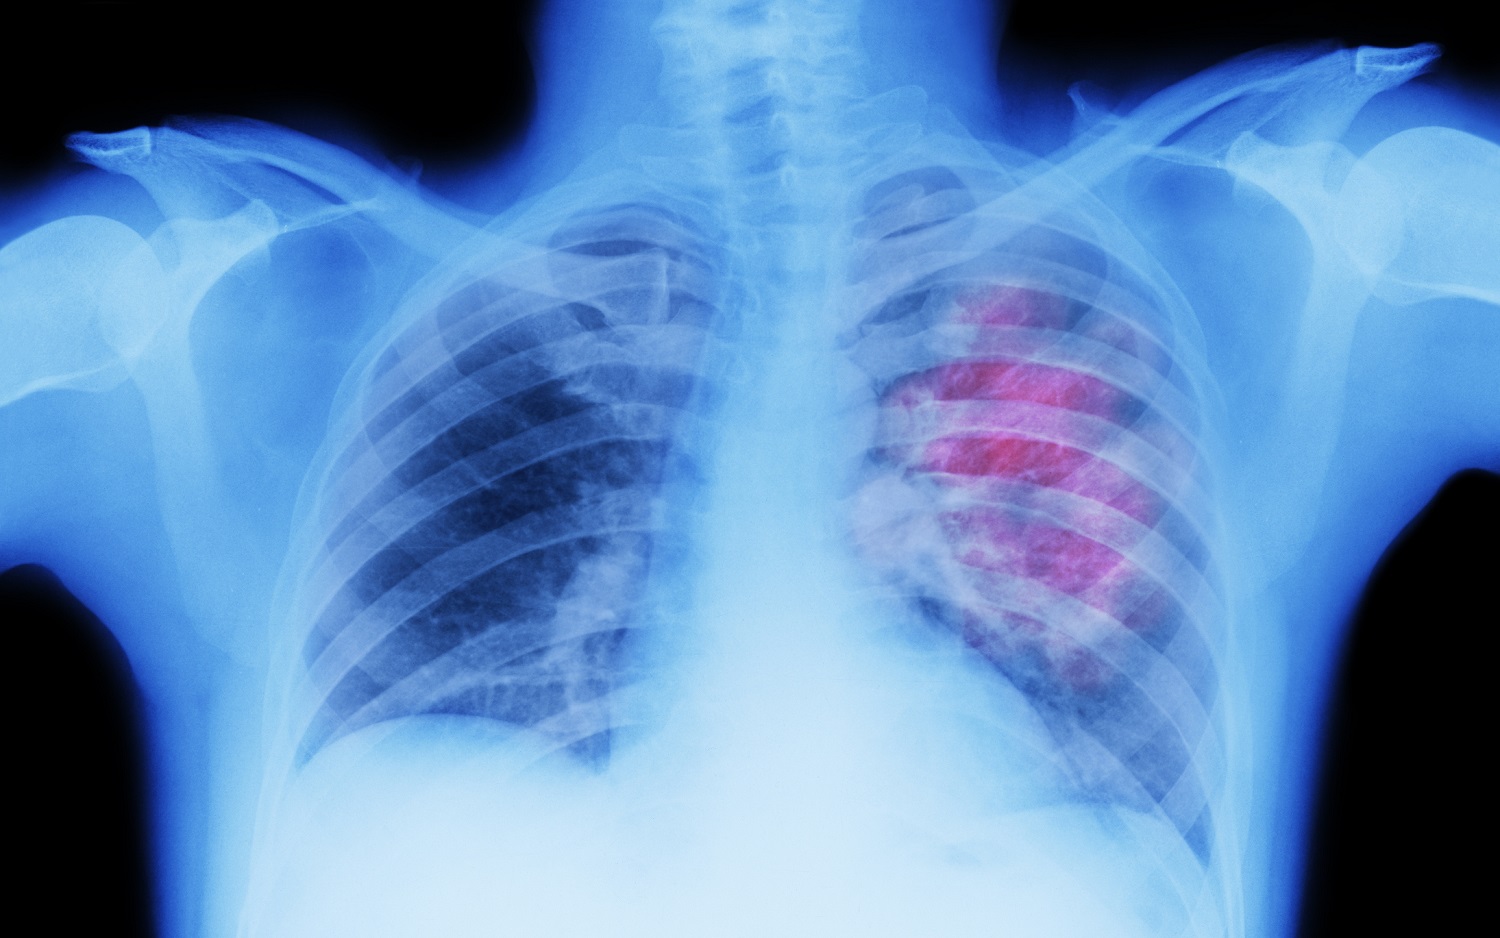

De otro lado, la fundación señala que hay ciertas enfermedades que pueden aumentar las probabilidades de que un paciente se desmaye. Por ejemplo, refiere el caso de las afecciones cardíacas, la anemia, la baja concentración de azúcar en la sangre y el síndrome de taquicardia postural ortostática (Stpo).